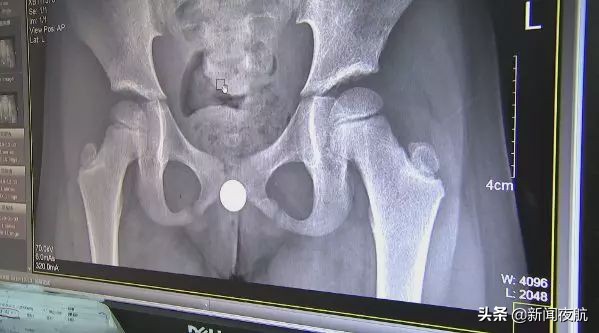

沈医生说,女孩*体下**有一个纽扣电池,后遗症还是比较严重的,女孩阴道里面大片烧焦,因为已经3、4天过去了,有一些已经变成了一个疤痕。

纽扣电池在体内烂掉了,引发肚子痛,医生连夜做手术将已经发黑的电池取了出来。小姑娘说,电池是自己玩的时候塞进去的。